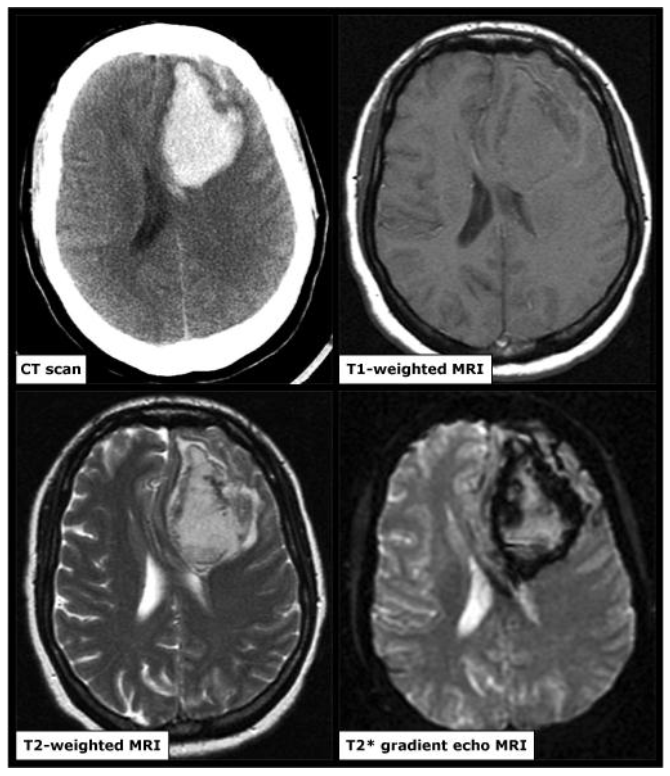

Hình ảnh CT và MRI của một bệnh nhân xuất huyết não cấp

Hình ảnh CT và MRI của một bệnh nhân xuất huyết não cấp trong thời gian 6 giờ kể từ khi xuất hiện triệu chứng. Hình ảnh CT sọ não thấy ổ tăng tỷ trọng nằm trong nhu mô thùy trán trái so với nhu mô não giúp khẳng định chẩn đoán xuất huyết não cấp. Trên MRI hình ảnh ổ xuất huyết này thay đổi trên các chuỗi xung: đồng tín hiệu trên xung T1 và tăng tín hiệu trên xung T2W và vùng viền giảm tín hiệu trên T2*.